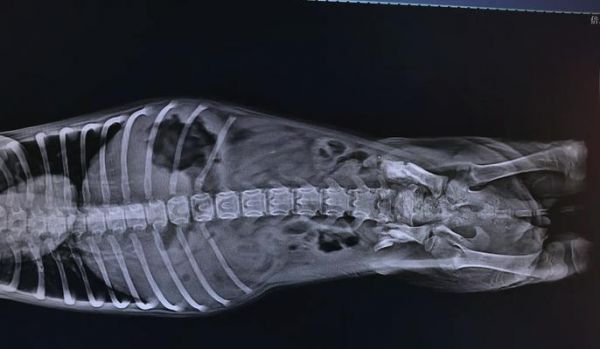

6.骨折类型与康复时间的关系:不同类型的骨折,康复时间也各不相同。

8.骨折部位对康复时间的影响:不同部位的骨折需要不同的康复时间。

9.幼犬骨折康复的阶段:幼犬骨折康复分为炎症期、修复期和重塑期三个阶段。

14.骨折幼犬康复时间的预估:根据骨折类型和部位,一般需要4至8周的时间。